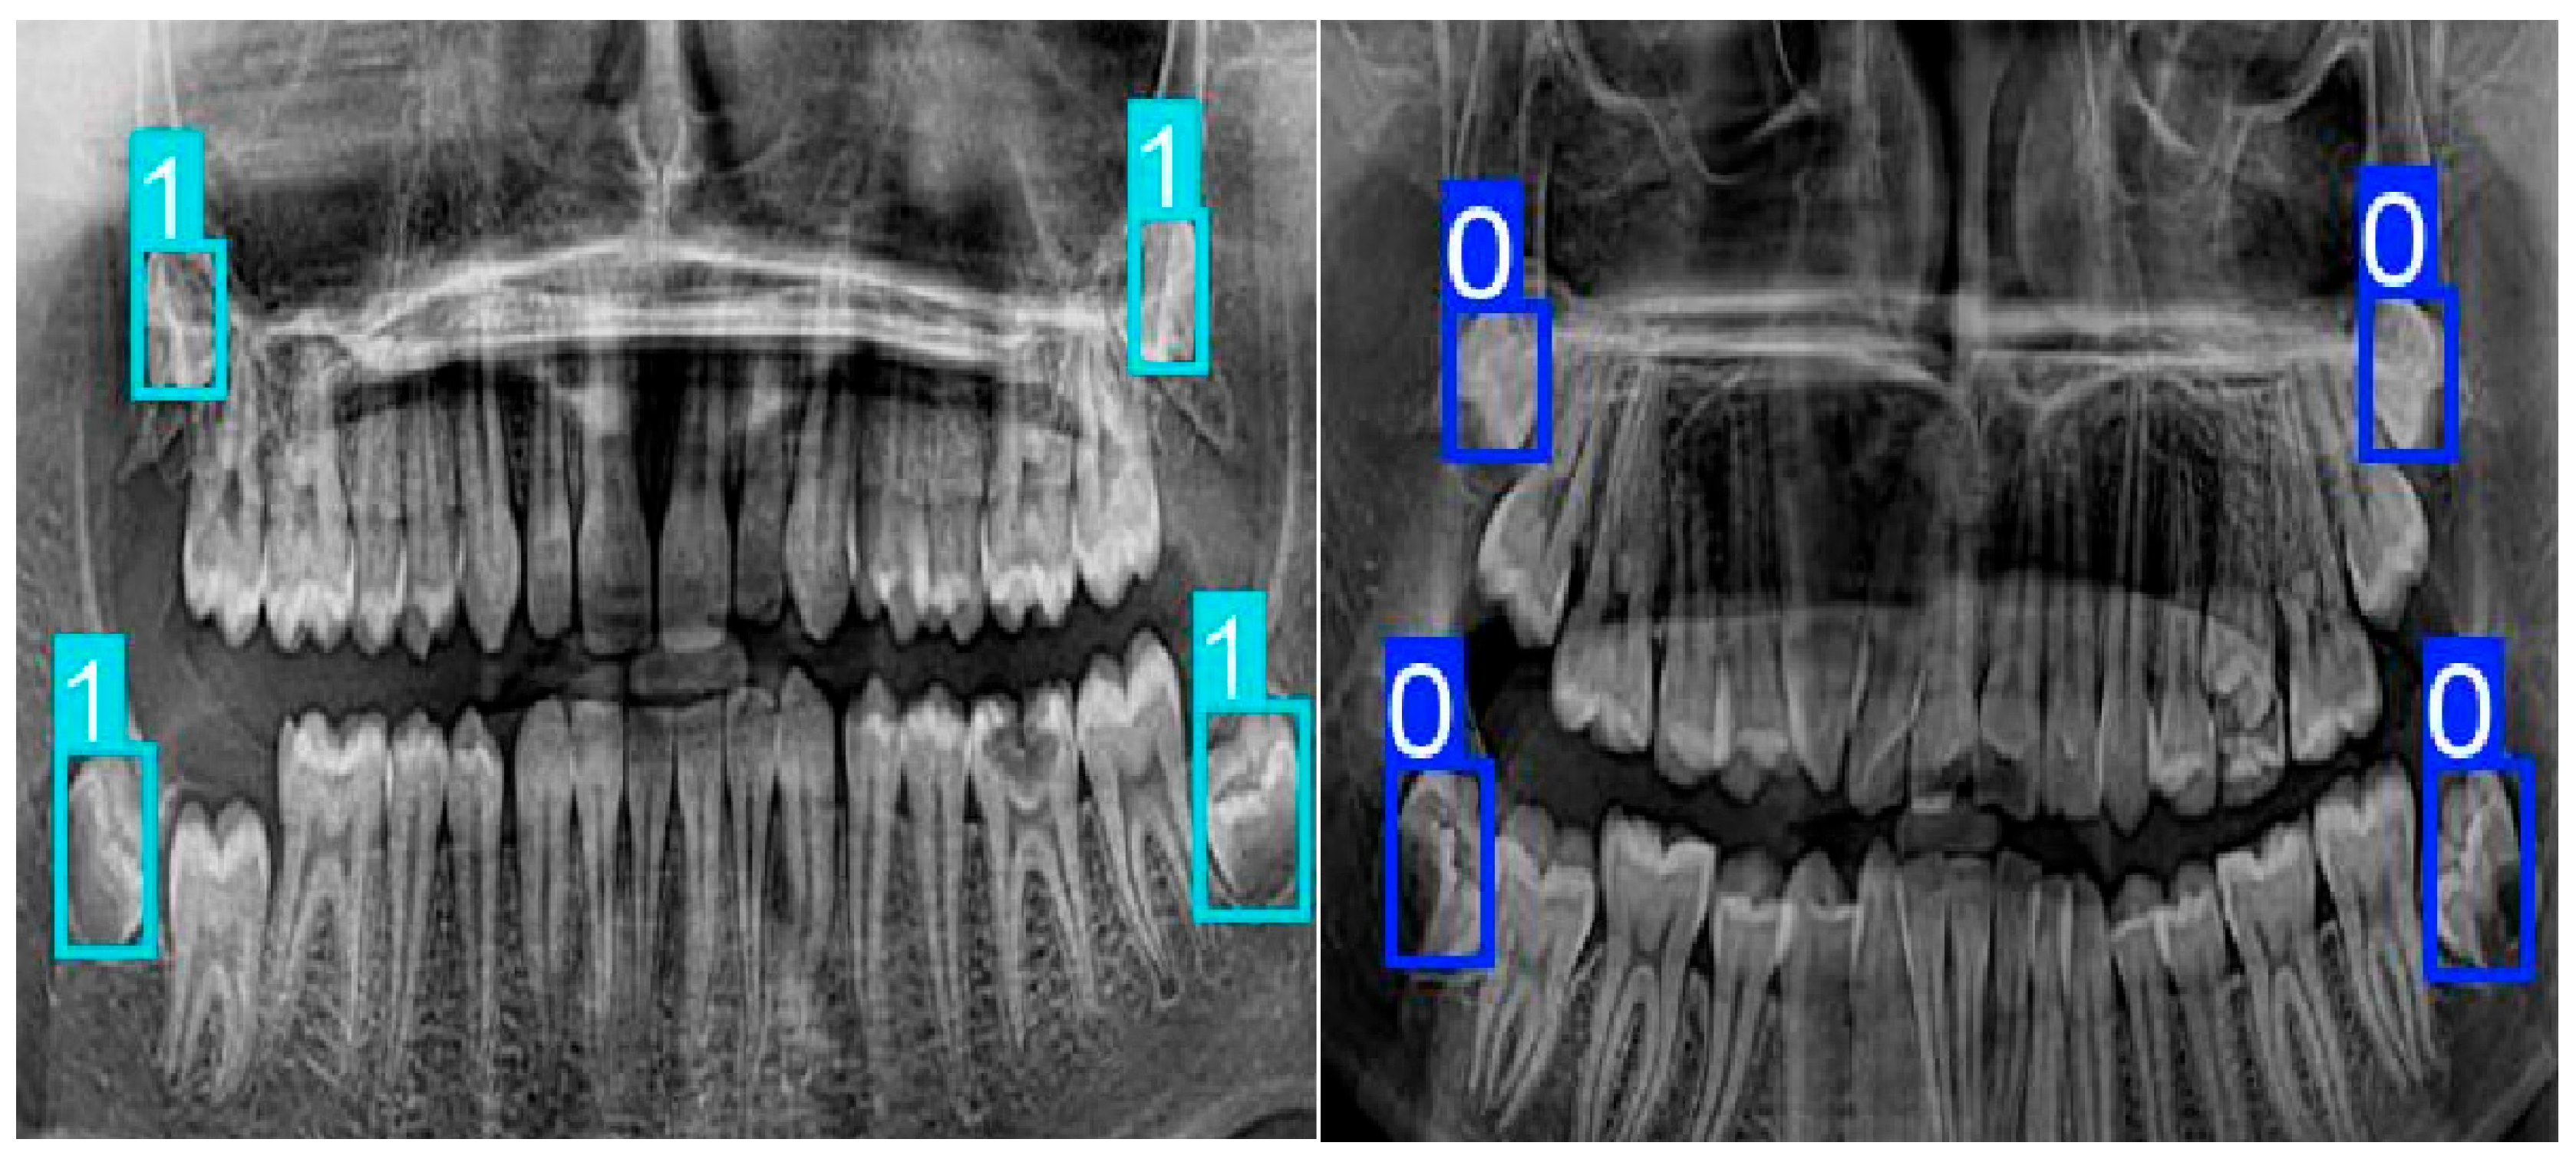

1. Introduction

2.2. Image Review and Annotation